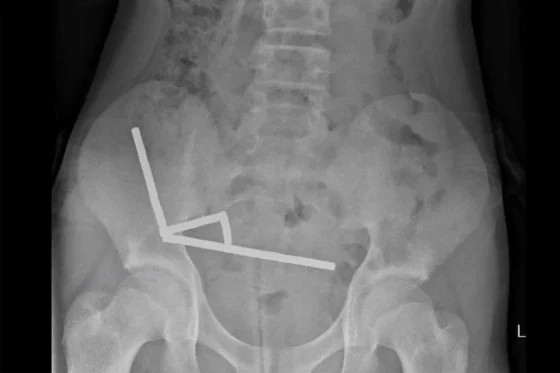

医療スタッフはX線検査で少年の腸内に約200個の小型ネオジム磁石が鎖状に固まっているのを発見した。

これらの磁石は互いに強く引き合い、腸壁を圧迫して血流を遮断し、その結果腸粘膜の一部が壊死した。医療スタッフは磁石と損傷した腸組織を同時に除去する手術を行い、少年の腸から5㎜×2㎜サイズの磁石200個以上を摘出した。